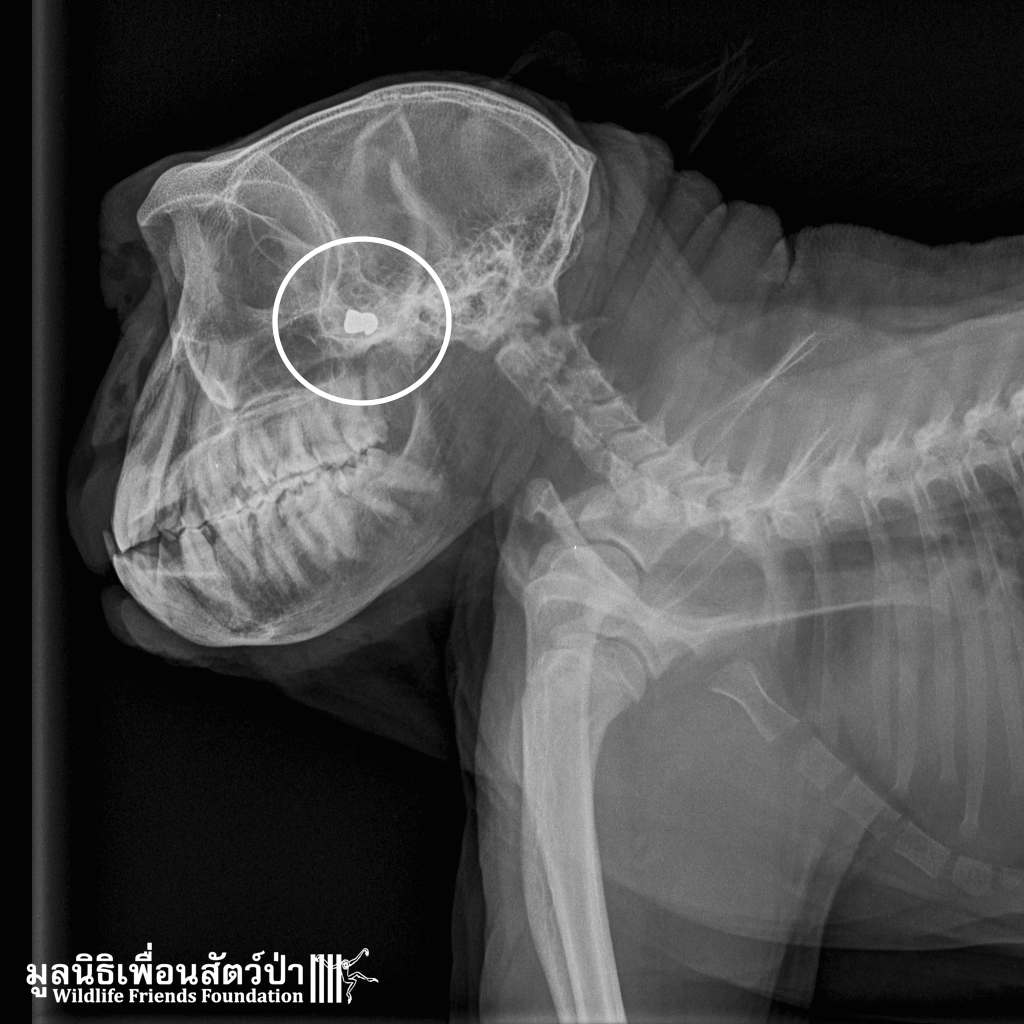

Late on Friday evening the WFFT Vet Team were called to attend an injured long-tailed macaque from an urban troop in Khao Wang, around 40km from the centre. The macaque had an injury to the face and had been found by locals walking about blindly.

On examining this male primate it was discovered he had an infected wound, which had caused swelling of his eyelids and closure of the eyes. X-ray confirmed that he had actually been shot between the eyes. The bullet had missed both eyes and time will tell whether it has damaged the optic nerve. The X-rays also showed that Frank, as he has been named, has suffered several bullet wounds in his life. Though he had been castrated this has obviously not resolved the human-animal conflict his troop is causing.

With daily treatment Frank’s wounds are improving and the swelling reducing. As his eyelids start to open It is clear that he still has some sight left and we hope in the near he will be able to return to the wild.